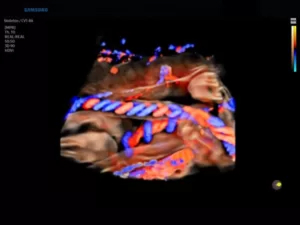

Режим PD (Power Doppler, энергетический)

Является разновидностью ЦДК, однако обладает большей чувствительностью к присутствию кровотока, чем цветовой доплер. Принцип работы PD-сканирования основан на анализе амплитуд всех эхосигналов допплеровского спектра, отражающих плотность эритроцитов в заданном объеме. Оттенки цвета (от темно-оранжевого к желтому) кодируют интенсивность эхосигнала.

Диагностическая ценность энергетической допплерографии состоит в возможности оценки васкуляризации органов и патологических участков. Методика не несет информации о средней скорости кровотока в отдельных элементах изображения, а регистрирует сам факт наличия кровоснабжения.

65.jpg

Рис.6. Плацента, энергетический доплер и 3D-режим.